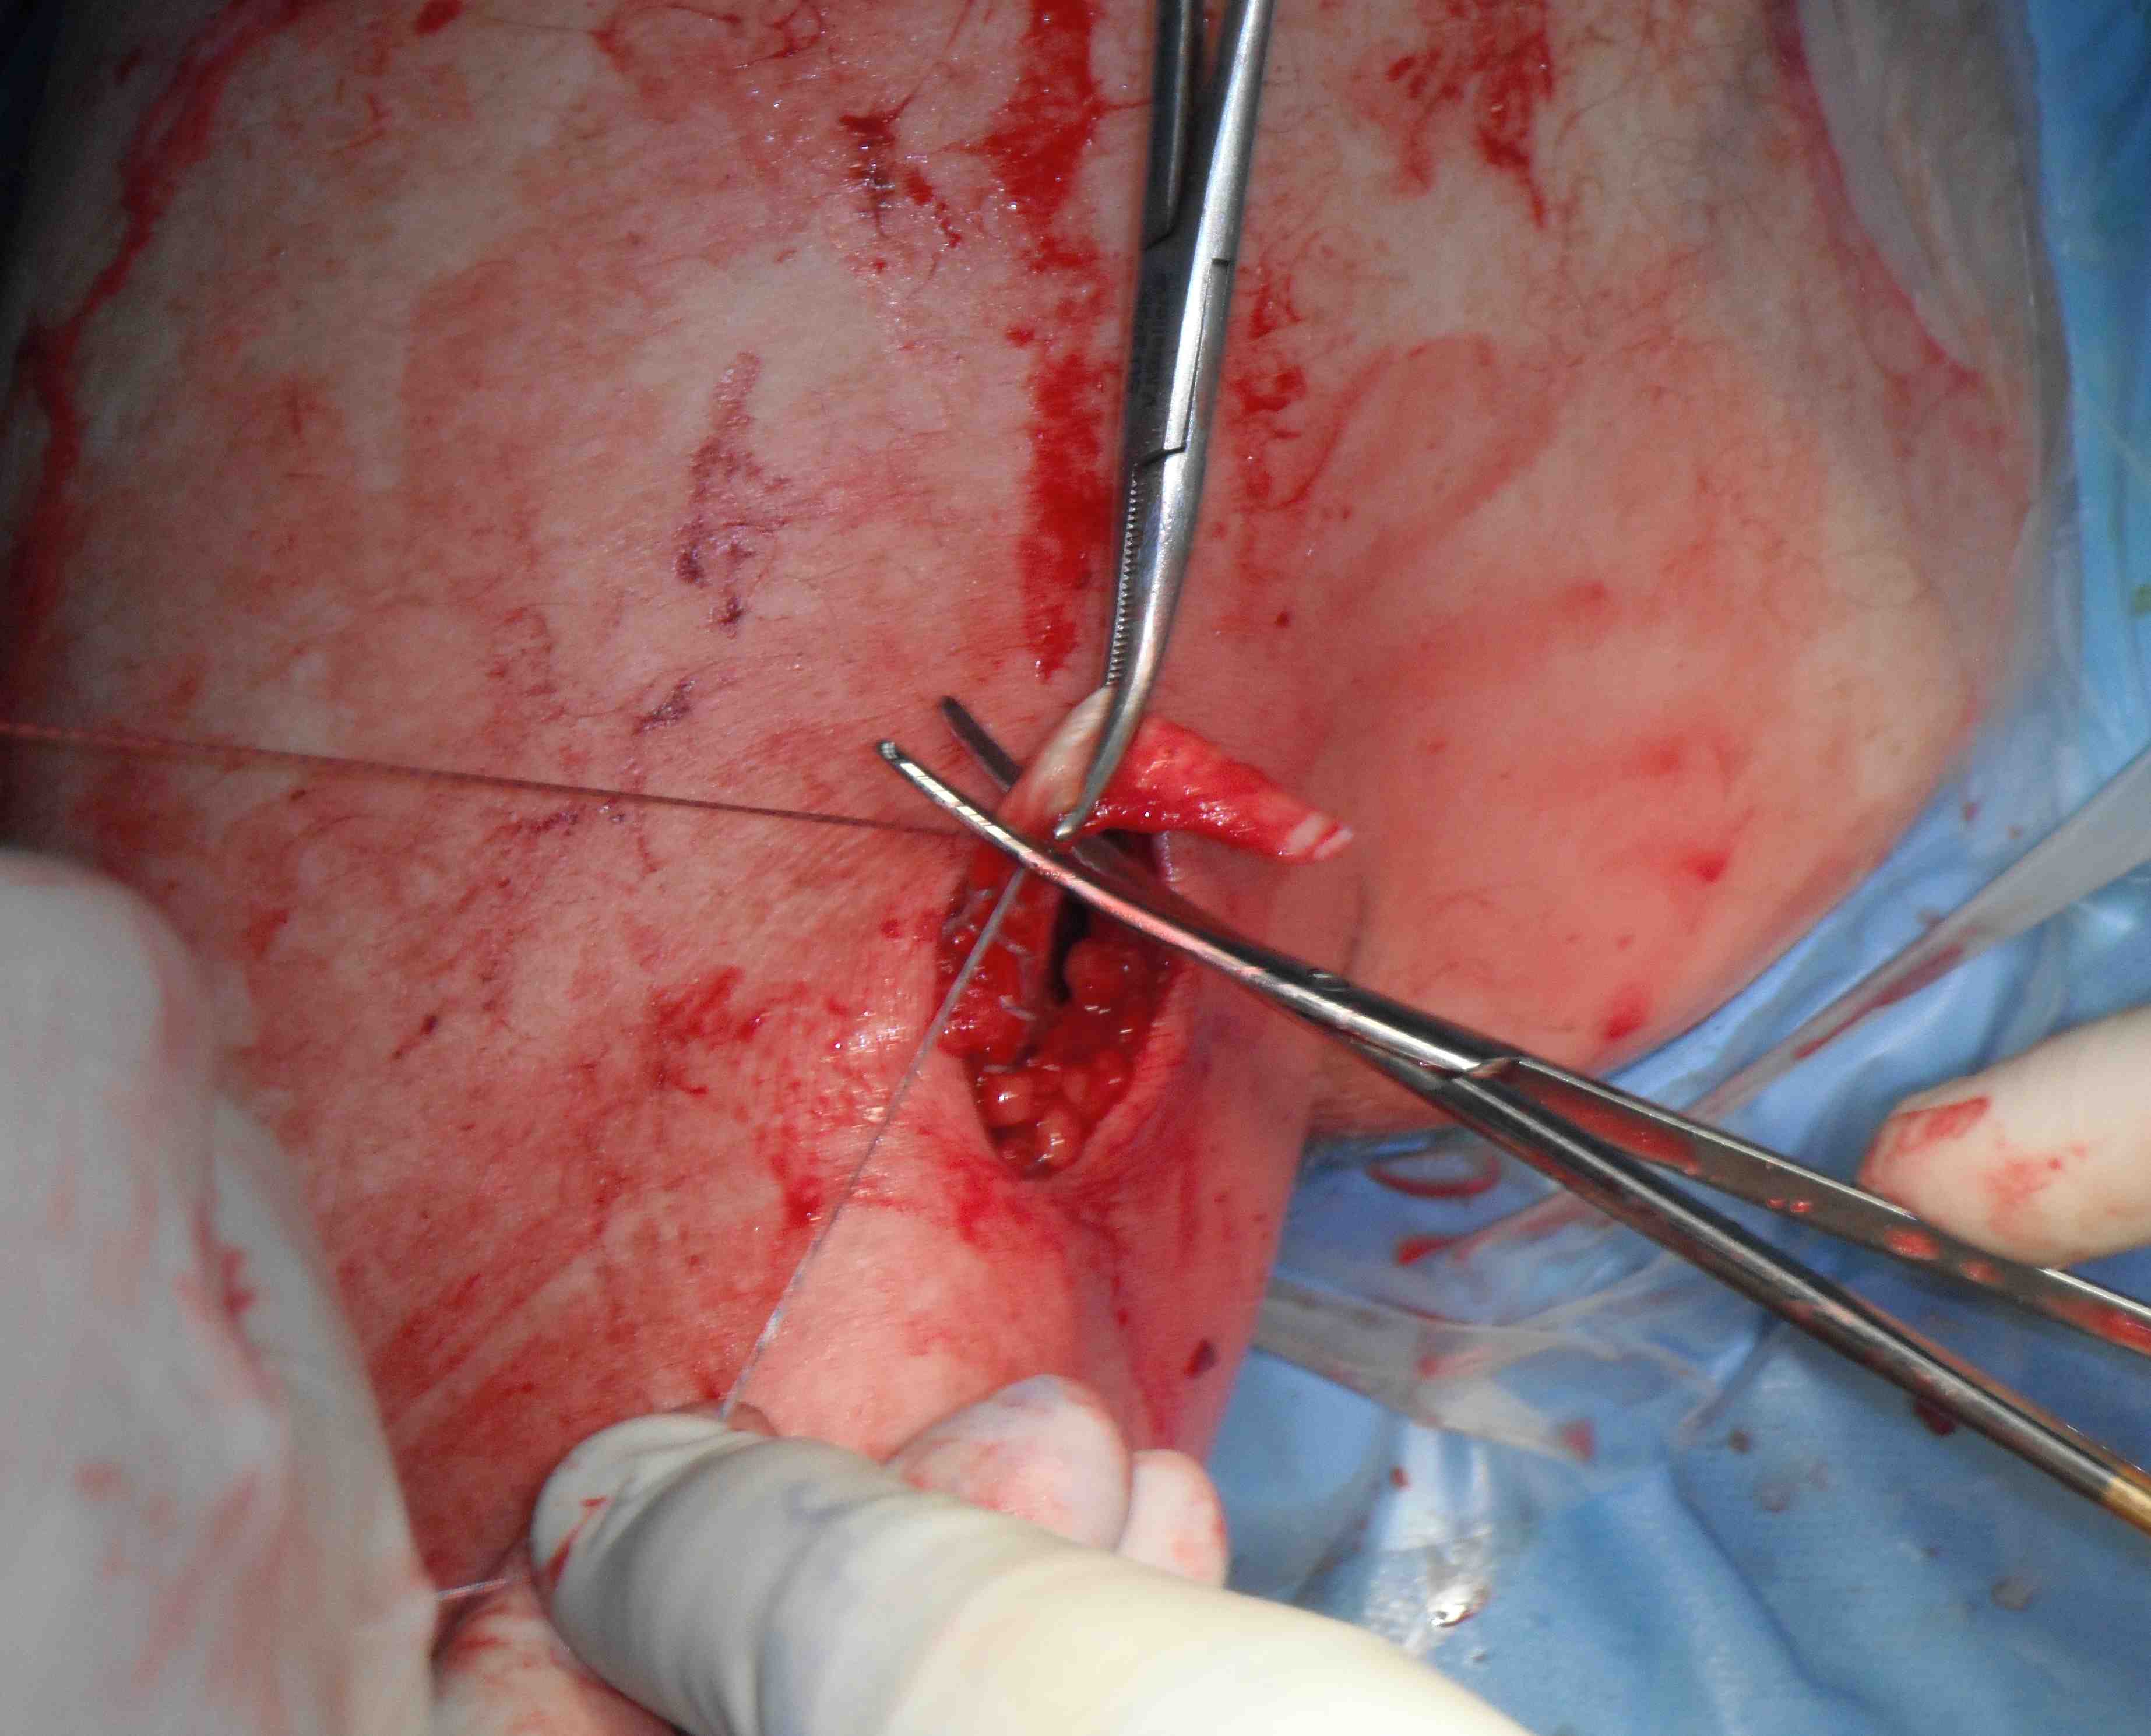

- arthroscopic biceps tendon release

- open approach to biceps

- incision centered on humerus below pectoralis tendon

- retract deltoid laterally / elevate pectoralis tendon / conjoint tendon medially

- find biceps tendon / shorten to 2cm of tendon / suture

- anchor biceps tendon